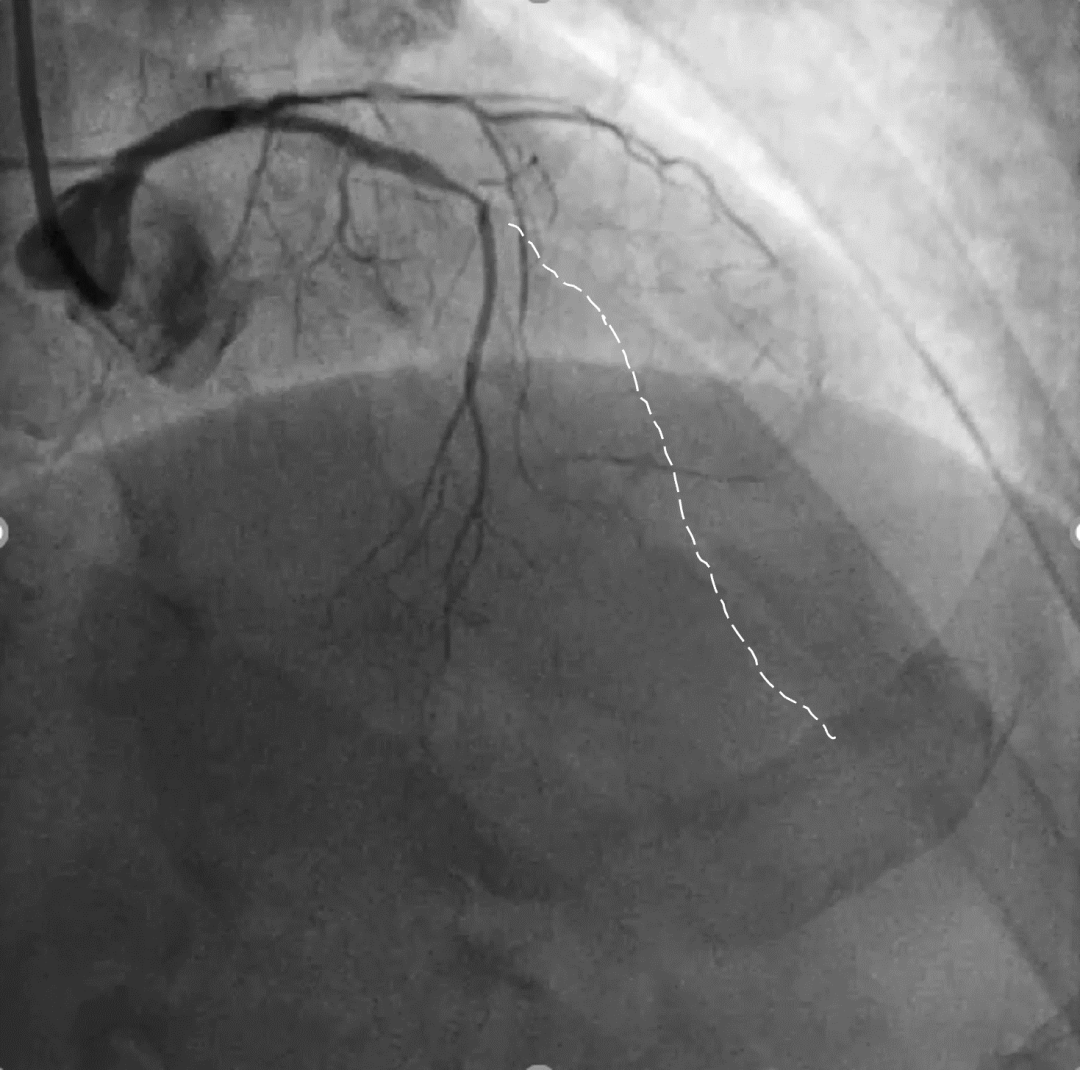

手术影像

左冠优势,LM、LCX未见狭窄,TIMI3级;LAD近段CTO,TIMI0级

RCA细小,近中段狭窄40%-50%,TIMI3级;远端可见LAD侧枝血流

策略讨论:近端纤维帽不清晰,LAD中段显影可见,闭塞段长度>20mm。间隔支逆供条件尚可。CTA提示LAD多发钙化。尝试正向开通,优选亲水性滑导丝,若失败,及时调整逆向策略。